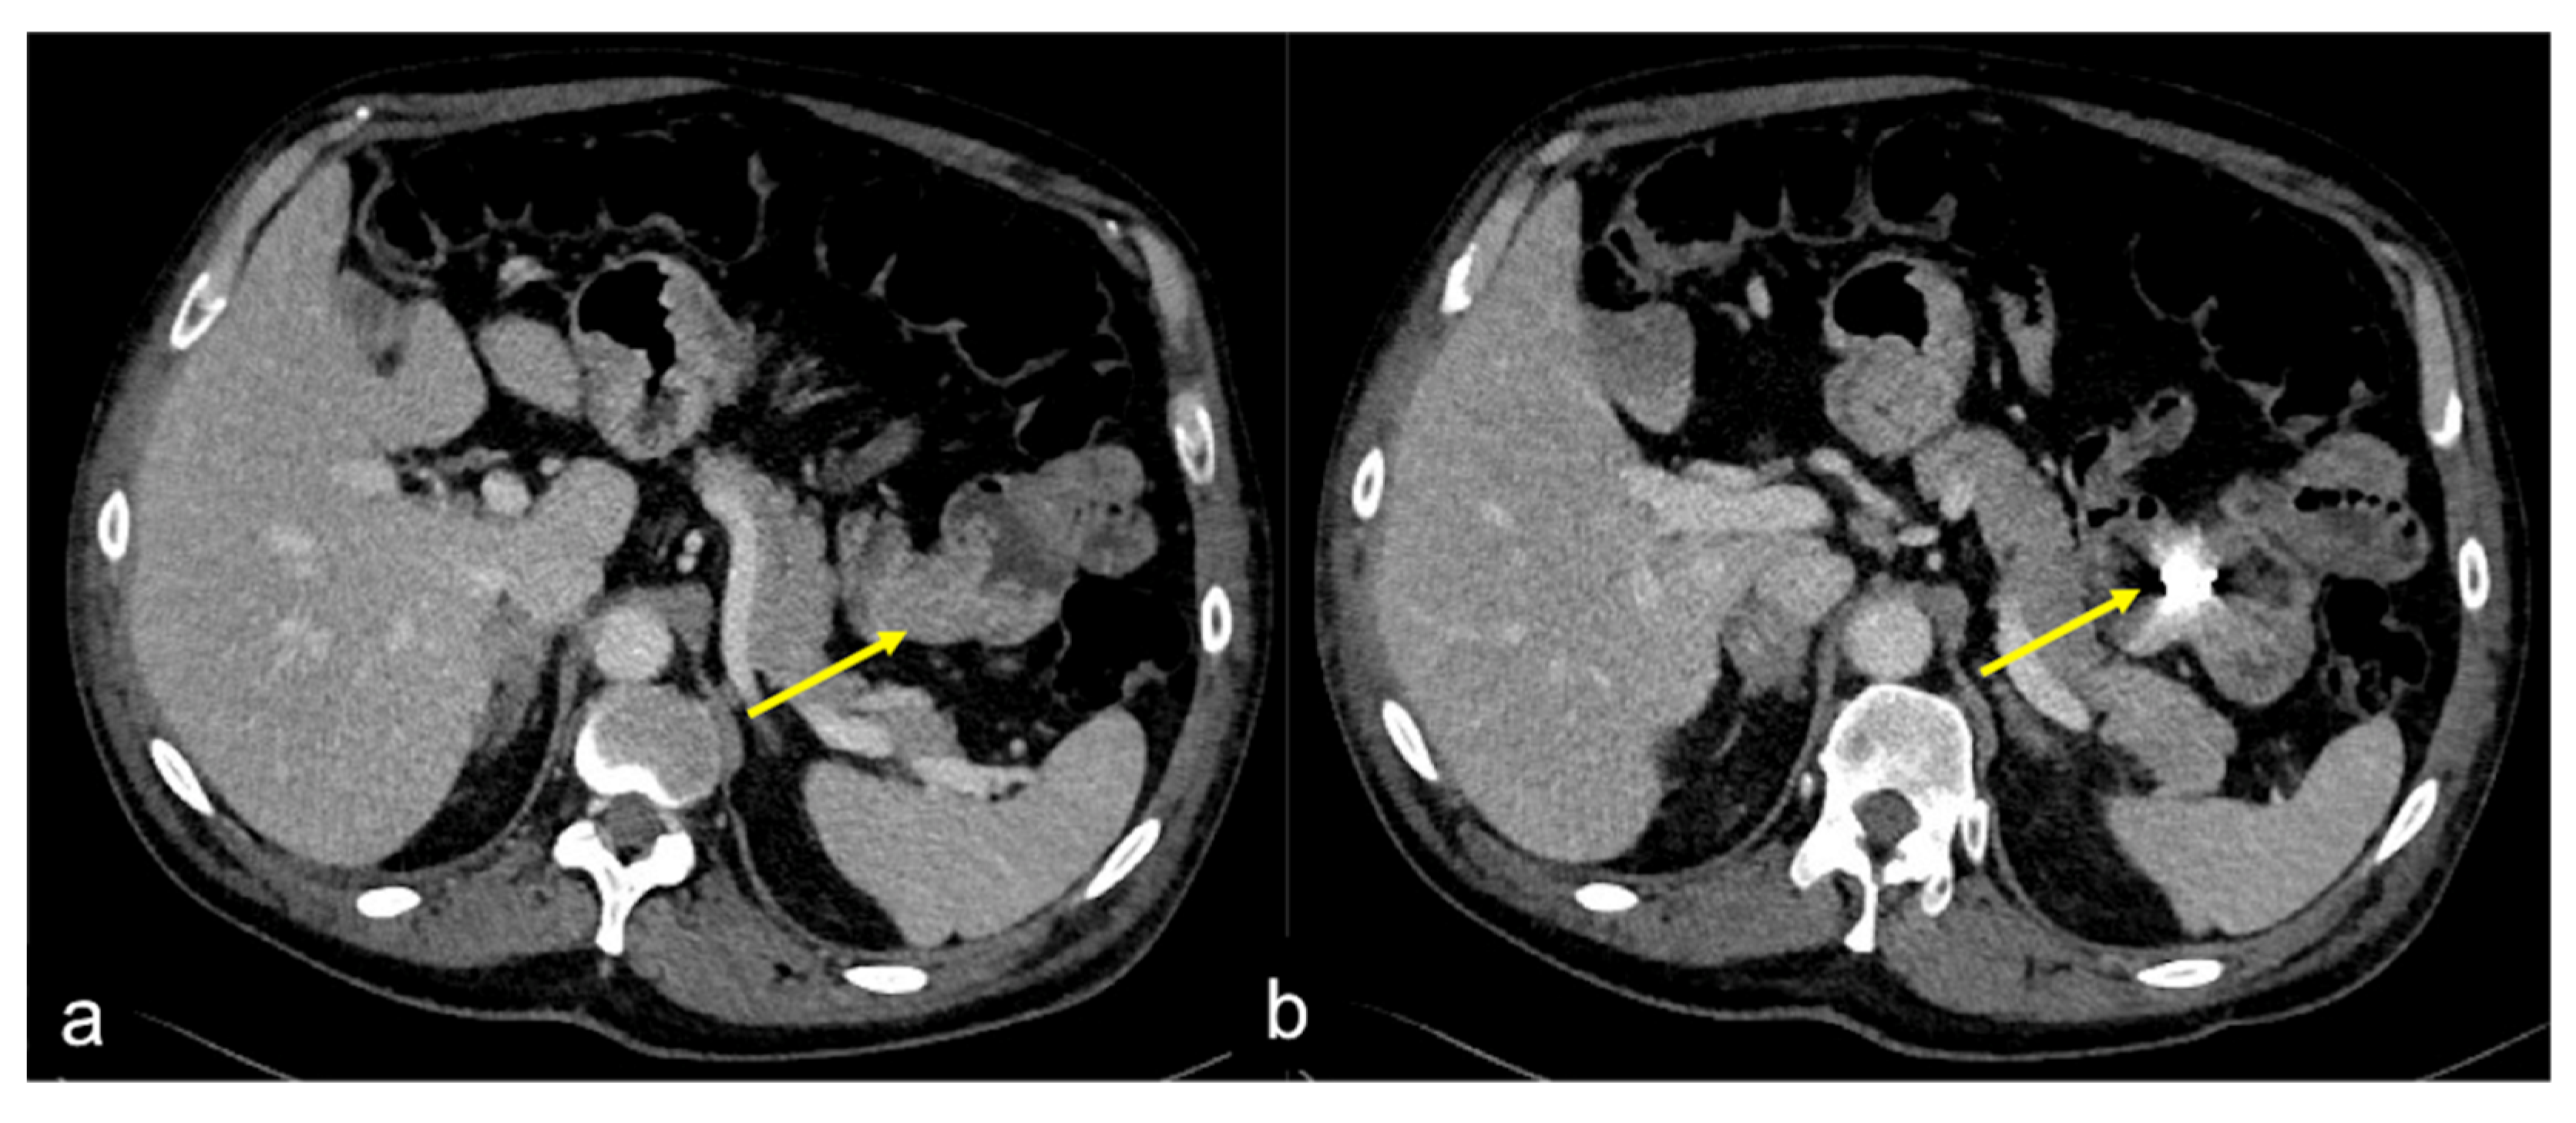

| Meckel’s Diverticulum (Figure 30) | Asymptomatic or, rarely, massive gastrointestinal bleeding. | A diverticulum with fluid or air content originating from the antimesenteric side of the distal ileum. |